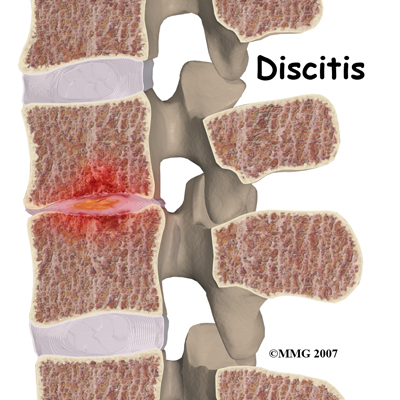

Discitis and vertebral osteomyelitis are rare in children. When a disc becomes inflamed and possibly infected, the condition is called discitis. If the vertebral bone becomes infected, the condition is called vertebral osteomyelitis.

Common symptoms of these conditions include refusal to crawl, sit, or walk and complaints of back pain. A limp and forward bending while placing the hands on the thighs for support are also common signs.

With discitis, the disc will appear narrowed on an X-ray or an MRI. Discitis usually occurs in children less than five years old.

Vertebral osteomyelitis tends to affect older children and adolescents. The vertebral bone and surrounding tissue including the disc can become infected. On X-ray or MRI the bone and/or tissue can show destruction. Fever of 102 degrees Fahrenheit or 39 degrees Celsius or greater is common in vertebral osteomyelitis.

Both discitis and vertebral osteomyelitis are treated with rest, as well as oral and IV antibiotics. A brace to support the spine may be suggested. With osteomyelitis surgery may be necessary to clean out the infection and/or to stabilize the spine.